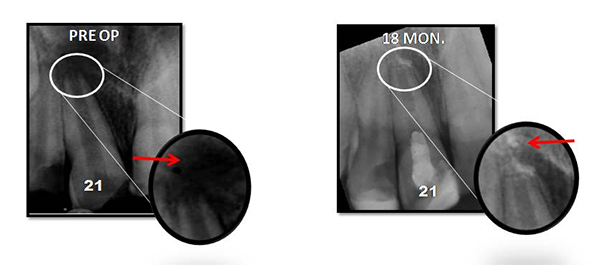

Regenerative Endodontic Procedure -

Naseem Shah -

PRF Mediated REP in 21 with 18 Months Follow Up

Complete Bony Healing, Apex Closed, Lateral Wall Thickening- 15.5%

Tanisha Konai -

PRP Mediated REP in 21 with 18 months follow up

Bone healing, Apical PDL formed, Apex Closed, Calcific Bridge formed in 21.

Vitality Positive

Amanulla  -

PRF Mediated REP in 22 with 18 months Follow up

Complete Bony Healing, Calcific Bridge Formed.

PRF Mediated REP in 21 with 26 Months Follow Up

Complete Bony Healing, Apex Closed, Lateral Dentinal Wall Thickened, PDL Apically